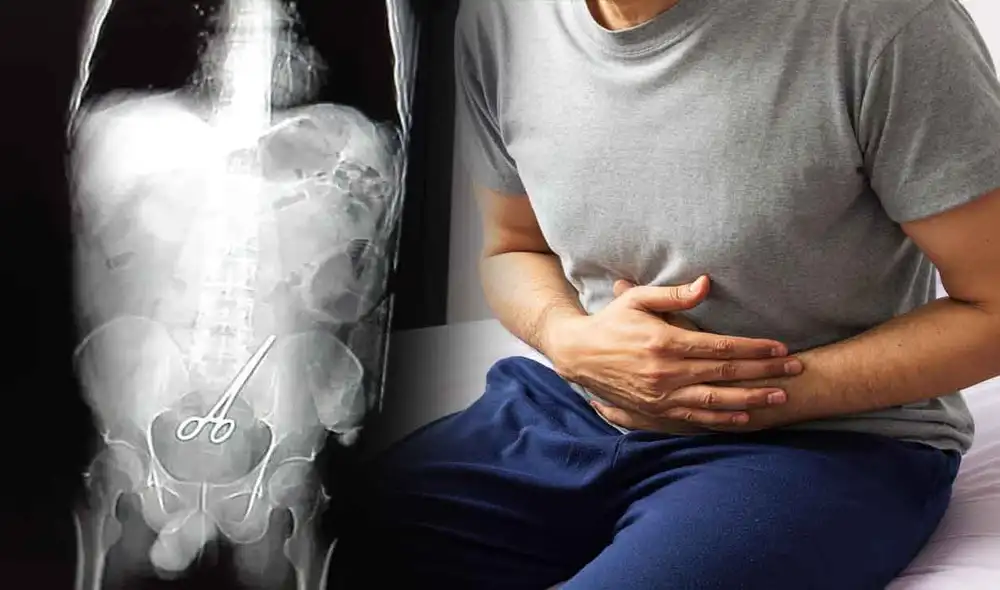

Hombre acude al hospital por dolor abdominal y encuentran tijeras quirúrgicas en su intestino

Un político de Brasil se llevó una gran sorpresa luego de enterarse de que el fuerte dolor abdominal que tenía se debía a la presencia de tijeras quirúrgicas en su intestino, lo cual se produjo debido a una mala praxis, puesto que los médicos del Hospital Regional de Colíder se olvidaron de extraer el instrumento cuando le extirparon un tumor, el último 20 de enero.

Se trata de Cleyton José Zanatta, concejal del municipio de Nova Santa Helena, estado de Mato Grosso, quien tuvo que retornar al hospital seis días después de haber pasado por una cirugía. Tras haberle practicado una tomografía computarizada, se descubrió el extraño objeto que habría sido olvidado por los médicos cuando suturaban el corte al culminar la intervención.

Debido al error médico, se le tuvo que volver a operar para retirar el instrumento quirúrgico. Foto: G1

Al también miembro del Partido de la Social Democracia Brasileña (PSDB) se le ordenó que pasara por una nueva cirugía para así retirar el peligroso objeto. Tras ello, el político se viene recuperando de esta negligencia médica, que ya está siendo investigada por la Secretaría de Salud del Estado (SES). “Tenía mucho dolor de cabeza, así que llamé al médico y me dijo que eso es en parte porque me dieron dos anestesias en menos de una semana. Pero ya estoy en casa, gracias a Dios”, declaró.